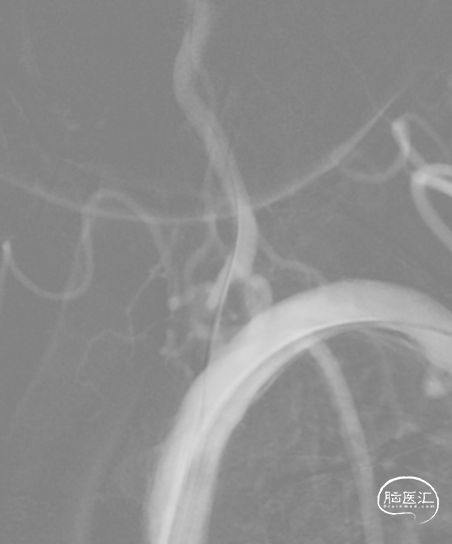

沿微导丝送入2.5mm*15mm球囊预扩张狭窄处。

沿微导丝送入3.0mm*16mm Bridge椎动脉雷帕霉素靶向洗脱支架到达目标位置。经手推造影确认定位后,缓慢加压释放支架。